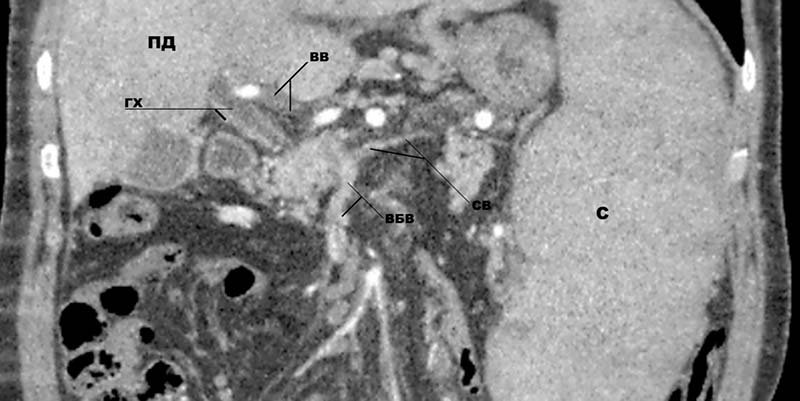

При выполнении компьютерной (КТ) или магнитно-резонансной ангиографии (МРТ) наблюдается дефект контрастирования в просвете ВВ (рис. 1), повышенное наполнение печени в артериальную фазу. [15, 47, 57, 58] Данные исследования, хотя и имеют второстепенное значение, но помогают, во-первых, определить протяжённость тромбоза, а во-вторых, верифицировать инфаркт кишечника, если таковой имеет место. [20, 24, 47]

Рис. 1. КТ-ангиография больной Б. с тромбозом воротной вены (фронтальная проекция). Определяются неконтрастируемый ствол воротной вены (ВВ), частично тромбированная верхняя брыжеечная вена (ВБВ), тромбоз с частичной реканализацией селезеночной вены (СВ), а также расширенный гепатикохоледох (ГХ) с утолщенными стенками (портальная билиопатия). ПД – правая доля печени; С – увеличенная селезенка.